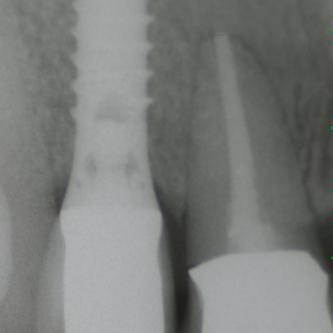

Exemple 12: Ici la pose de deux implants est envisagée, mais la hauteur d'os est insuffisante pour le deuxième implant. Le sinus (qui est une cavité creuse) est à moins de 6 mm de la surface de l'os. Idéalement il faudrait 10 mm d'os.

Exemple 12: Il faut donc relevé le sinus avec une greffe d'os avant de poser l'implant (Sinus lift).

Exemple 12: Les moignons vissés sur les implants 6 mois plus tard.